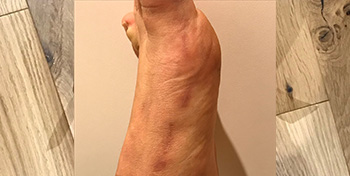

- Ganglion located on the side of the ankle, causing much discomfort during hikes or when wearing ski boots. US aspiration had been unable to fully drain it.